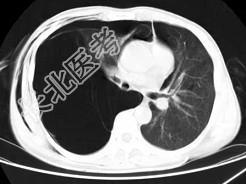

- 单项选择题男,32岁, 被车撞伤后1小时,请结合影像图像选择其最可能的诊断为 ( )

A、右侧气胸

B、右肺不张

C、右侧气胸并皮下纵隔气肿

D、右侧肺大疱并皮下纵隔气肿

E、支气管断裂